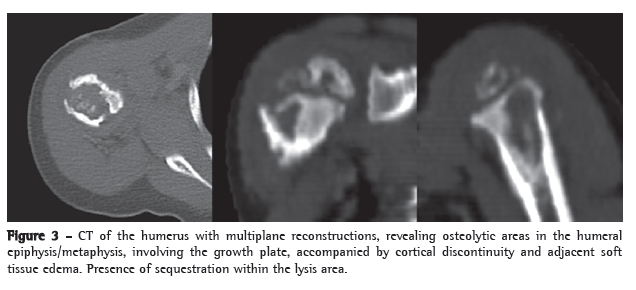

Complementary examinations revealed the following: leukocytes, 8,200 (9% rods and 66% neutrophils); erythrocyte sedimentation rate, 32 mm/h; C-reactive protein, < 6.0 mg/L; normal urine sediment; normal chest X-ray; and strongly positive PPD result, 18 mm. A CT scan of the humerus revealed multiple lytic lesions in the proximal region of the humerus, involving the epiphysis, the metaphysis and the proximal diaphysis, as well as cortical discontinuity and adjacent soft tissue edema (Figure 3).

The patient was discharged on post-admission day 19. He was in good clinical condition and had no fever or pain. Subsequently, monthly X-rays and another CT, performed 6 months later, revealed a decrease in the bone lesion, with reestablishment of the cortical contour, marked bone sclerosis, residual ill-defined lytic areas in the epiphysis and involution of the soft tissue edema.

Lytic and sclerotic bone lesions with periosteal reaction characterize the radiographic lesions. In the case described here, the CT findings in the epiphysis, the metaphysis and the diaphysis were consistent with previous descriptions in young patients. Older children usually present only metaphyseal changes.(4)